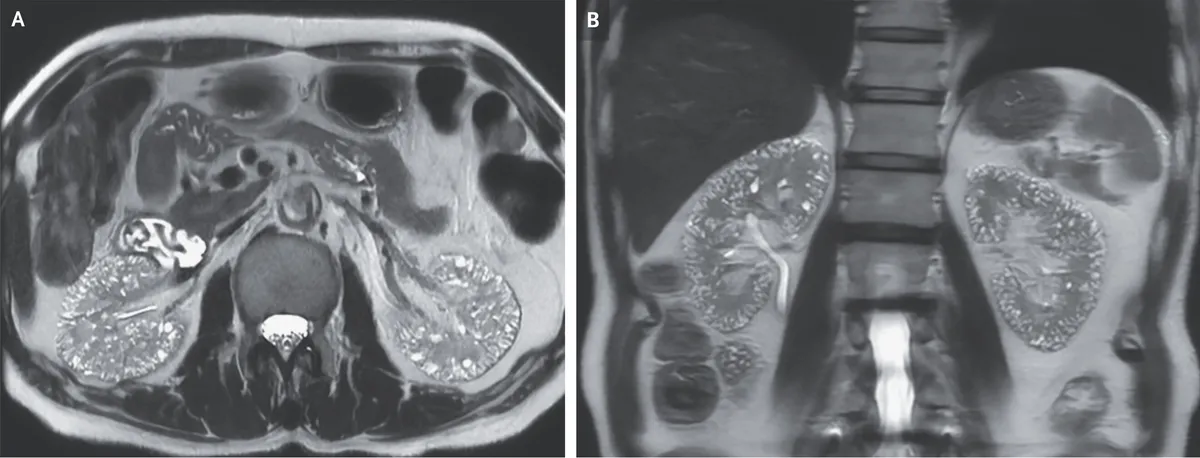

O paciente negava qualquer histórico familiar de doença renal cística. A RM ponderada em T2 revelou numerosas microcistos localizados no córtex e na medula de ambos os rins (Imagem abaixo - Painel A, corte axial; Painel B, corte coronal).

Foi feito o diagnóstico de microcistos compatíveis com nefropatia induzida por lítio. O uso de lítio está associado a diversos efeitos nefrotóxicos, incluindo diabetes insipidus nefrogênico, acidose tubular renal e nefropatia túbulo-intersticial crônica.

Microcistos de 1 a 2 mm podem ser observados em exames de imagem em pacientes com nefropatia túbulo-intersticial crônica induzida por lítio. O paciente permaneceu em tratamento com agentes alternativos para o transtorno bipolar. Após 2 anos de seguimento, a função renal manteve-se estável.